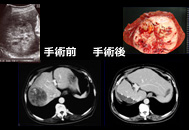

肝臓がんの診断はどのようにするのでしょうか?

大まかにわけて以下があげられます。

- 画像診断:腹部超音波検査(エコー検査)、CT/MRI、血管造影(カテーテル検査)

肝臓がんの画像診断

画像を組み合わせることで早期診断が可能

肝臓がんの画像診断

総合画像診断により正確な診断ができ、治療法の選択に有用である

肝臓がんの手術